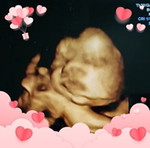

34w3d แม่ๆบ้านไหนมีอาการแบบท้องตึงมากๆมั้ยคะ ขอสอบถามหน่อย ท้องแรกยังไม่มีประสบการณ์

ตึกเป็นก้อนเฉพาะที่ น้องโก่งตัว ตึงทั่วท้อง ท้องปั้นแข็งคะ